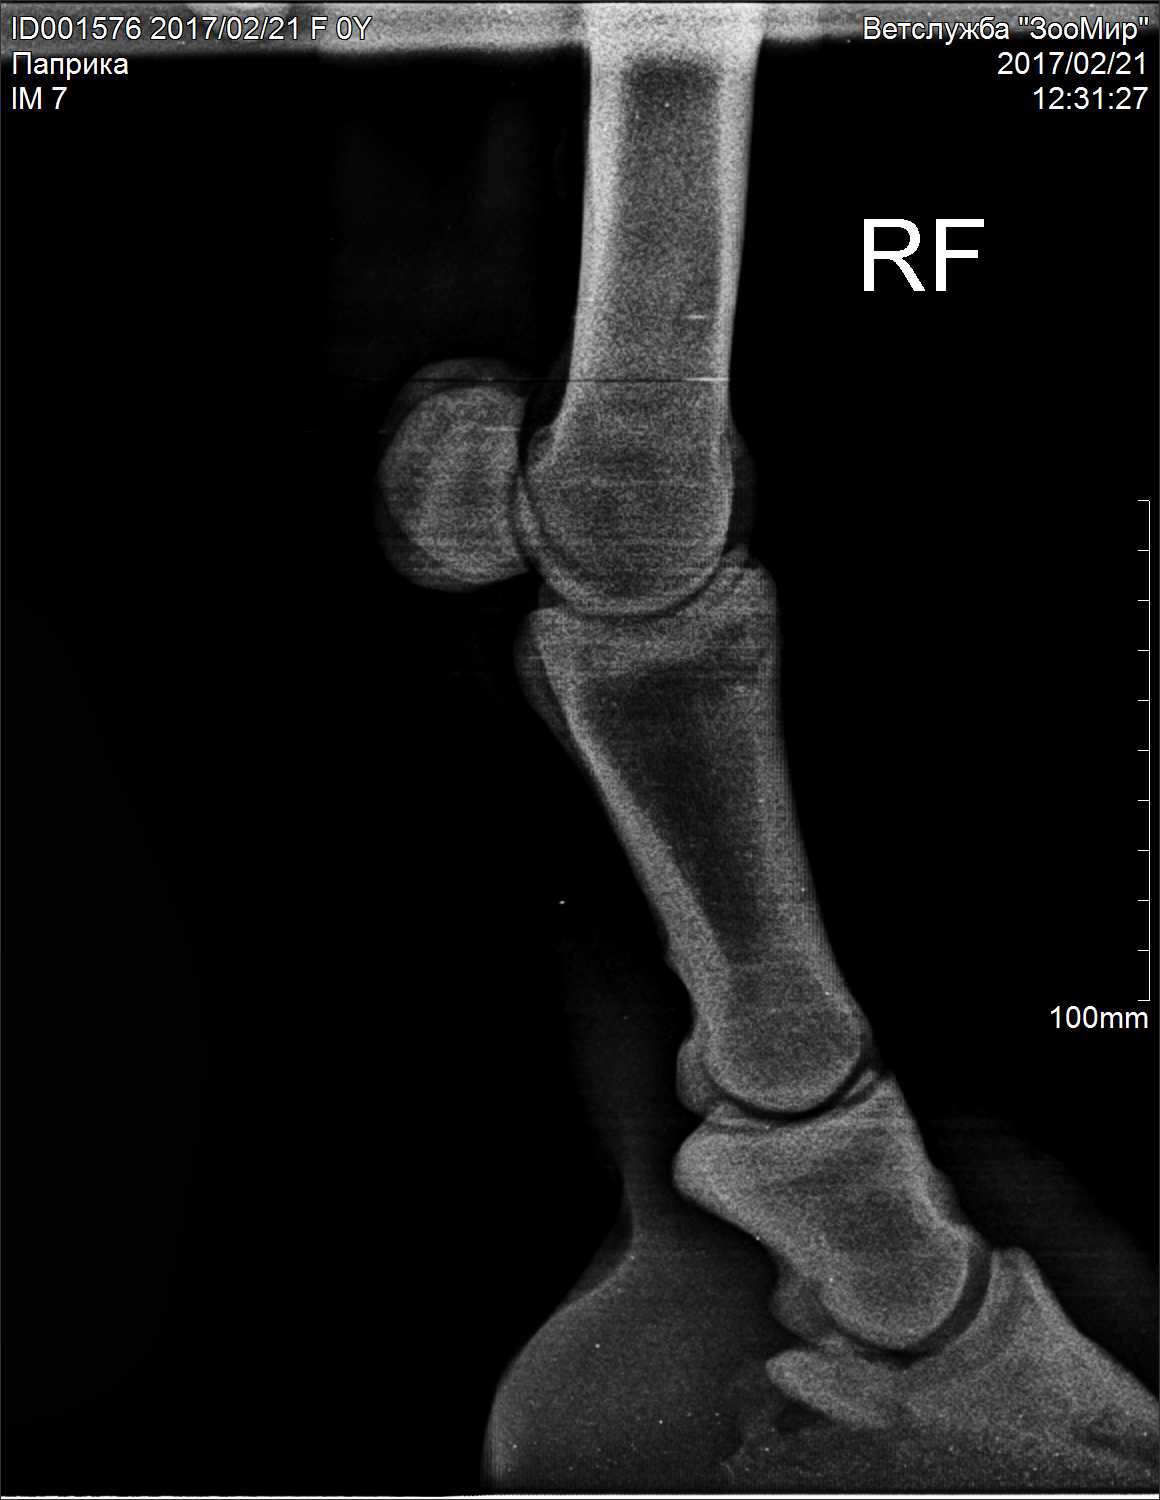

Добрый вечер!!! Помогите пожалуйста разобраться с такой ситуацией: моя лошадь стала хромать на переднюю правую ногу, лошади в мае будет 4 года, заезжена недавно. Работала 2 раза в неделю на корде, один раз верхом. Выгул ежедневный сено вдоволь, овёс пол ковша. Меня это забеспокоило и я вызвала рентген. Врач по снимкам мне сказал, что у нас киста в ПЛ ноге в челночной кости и синдром целующихся позвонков. Из лечения сказал ковать на круглые подковы, 5 фильц, поднимать пятку (лошадь не ковалась). Если подкованная будет хромать, колоть Бонефос. Лошадь молодая и с характером, блокады сделать было невозможно, выдирает ноги. Рентгенили тоже под седацией, но ноги все равно выдирала. Другой врач сказала что у нас перелом мякишного хряща, кисту не наблюдает. Я в панике! ((( Пожалуйста посмотрите снимки, все ли так серьезно?